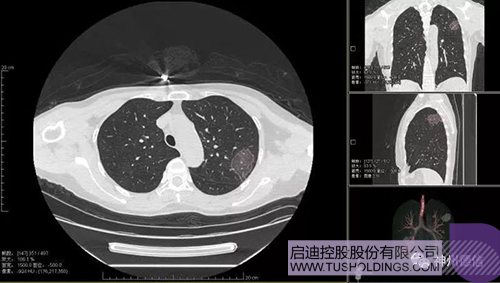

神州德信新冠肺炎检测及智能量化分析系统

开云手机入口_开云(中国)战略投资企业神州德信作为国内领先的肺部影像人工智能企业,针对新型冠状病毒肺炎开发了智能检测及量化分析系统,并在陕西、重庆等地定点医院投入使用。该系统在疑似病例大规模快速筛查及精准诊断方面发挥了重要作用,特别是其具有的肺炎患者临床影像跟踪量化随访功能,为快速有效阻断疫情扩散提供了有力武器。